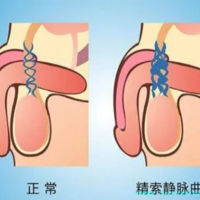

检查项目:激素六项、宫腔镜评介子宫腔内环境;精子DNA碎片率(若关联)。

方案调整:如头一次为长方案失败,医生可能改用拮抗剂方案降低卵巢刺激。